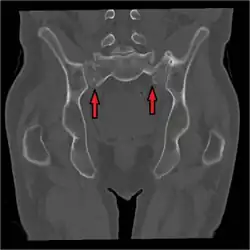

Bilateral sacral fractures arrow